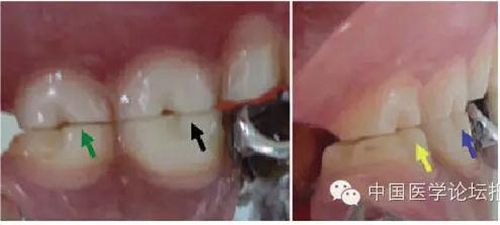

這種咬合接觸的結(jié)果是局部的咬合力集中在凸點(diǎn)接觸的位置,不能被有效分散,可造成受力部位牙體、牙周組織的應(yīng)力集中。最常見的表現(xiàn)是后牙頰舌向呈對(duì)刃關(guān)系,另外還常見于不完全遠(yuǎn)中關(guān)系或不完全近中關(guān)系的情況,此時(shí)從近遠(yuǎn)中方向來看,上下后牙牙尖之間凸凸相對(duì)(圖3)。

圖3 后牙凹凸接觸關(guān)系